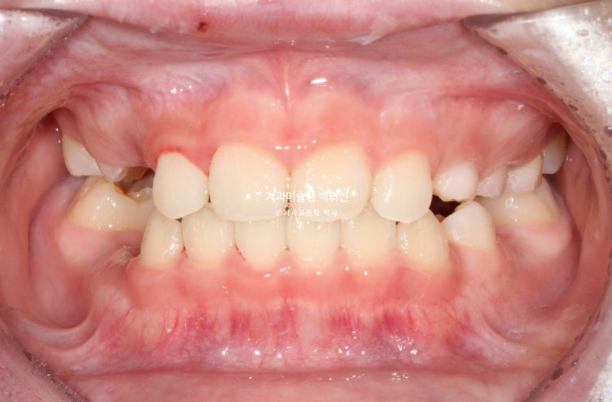

2022년 8월 내원한 어린이 입니다.

앞니 반대교합과 비대칭 치료를 위해 오셨습니다.

앞니 뿐 아니라 송곳니, 일부 어금니까지 거꾸로 물리는 상황입니다.

앞니 반대교합은 프리올소와 같은 장치로 간단하게 넘겨줄 수 있지만 더 큰 문제는 비대칭입니다.

아래앞니와 함께 아래턱이 우측으로 돌아가 있습니다.